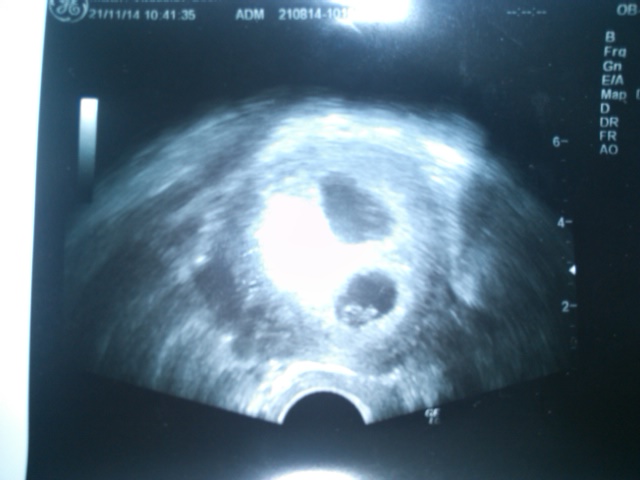

Jinak obrázky už mam dva, z první kontroly v 8mem týdnu a pak z 9teho, je tam jen takovej flíček.

Na kontrolu jdu v pondělí a dostanu průkazku a protože si nejsem jistá,jestli jsem se skoro před 14ti dny pochlubila,tak se pochlubím i teď.